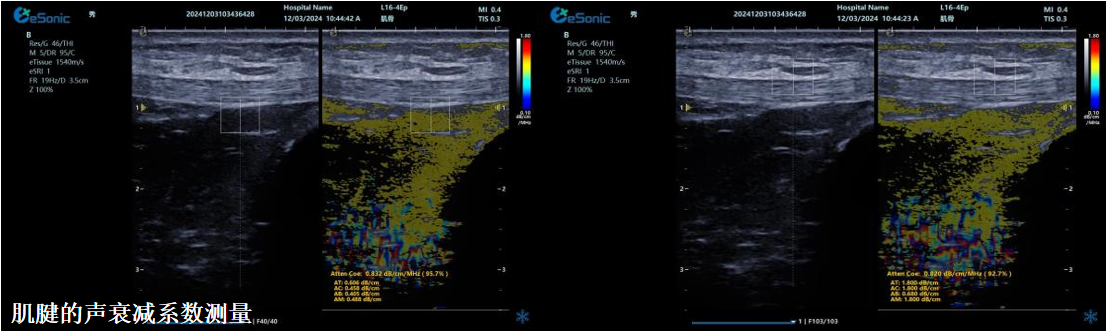

ATI高级声衰减成像

?独有的幅度损失的衰减方法ALA,准确性高,稳定性好,实时性好?业界唯一支持凸阵与线阵两种探头?支持多个取样框?提供两种显示单位

肌骨领域的应用

?肌腱炎症或损伤的评估?肌肉拉伤的定位?关节磨损或炎症的诊断?骨质疏松的早期发现和监测